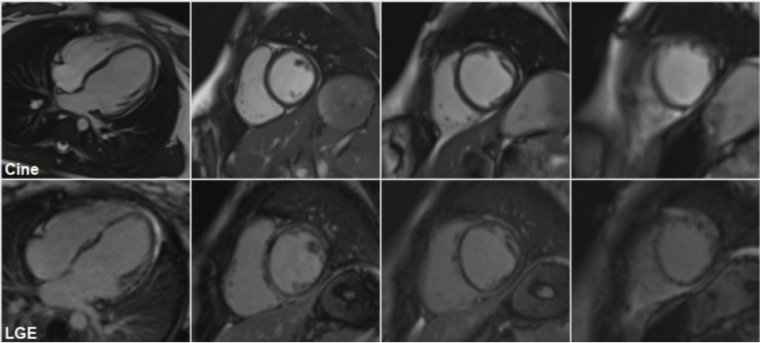

A repeat cardiac MRI was performed on March 2023 (figure 3):

Figure 3: Cine (top) cardiac MRI frames, demonstrating a mildly dilated LV cavity, with thinning of the apical segments and LGE (bottom) cMRI frames showing an almost circumferential ring-like appearance of gadolinium enhancement at the base mid cavity, extending apically.

This confirmed the presence of left ventricular dilatation (LVEDV 101 mL/m2, z+2.6; LVESV 57 mL/m2, z+6.4) with reduced global systolic function (LVEF 43%). There was thinning of the apical segments and regional wall motion abnormalities, affecting in particular the mid cavity to apical septum and the apical anterior wall. The left atrium was not dilated. There was extensive subepicardial and mid wall LGE in a nonischaemic pattern, involving the inferior, lateral, anterior wall and septum with an almost circumferential ring-like appearance at the base mid cavity, extending to the apical segments. RV volumes were again normal with preserved global systolic function.